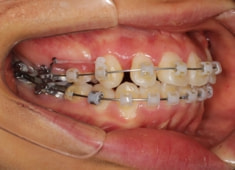

治療開始時

治療開始から11ヶ月後